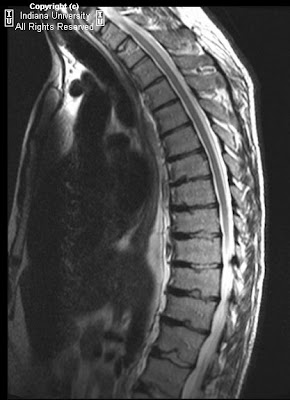

Neuroradiology On the Net: Scheuermann's disease (adolescent kyphosis)

Neuroradiology On the Net: Scheuermann's disease (adolescent kyphosis) from 2.bp.blogspot.com

Familial scheuermann disease is characterized by kyphotic deformity of the spine that develops in adolescence. Scheuermann, or scheuermann's, disease (juvenile kyphosis) is a deformity in the thoracic or thoracolumbar spine in which pediatric patients have an increased kyphosis along with backache and localized changes in the vertebral bodies. First and largest charity in the world solely dedicated to help those of us affected by scheuermann's disease/kyphosis. It affects less than one percent of the population and occurs mostly in children between the ages of 10 and 12. Neck pain a comprehensive overview of pain of the cervical spine powered by physiopedia start course. The treatment of scheuermann's disease or scheuermann's kyphosis is a matter of debate in which some researchers believe that treatment is not required as it is a benign condition whereas some are of the opinion that treatment should be given to those individuals who are immature. 1, 2 see the image below. Scheuermann's disease causes some od the spinal vertebrae to grow in a wedge shape instead of a normal cylindrical shape. Scheuermann's disease is considered to be a a form of juvenile osteochondrosis of the spine. The small bones (called vertebrae) that make up the spine are usually rectangular. Wedging of the vertebrae causes this condition. It affects boys and girls with a slightly higher number of boys affected. Scheuermann disease, also known as juvenile kyphosis, juvenile discogenic disease 11, or vertebral epiphysitis, is a common condition which results in kyphosis of the thoracic or thoracolumbar spine. Morbus scheuermann, adoleszentenkyphose, adoleszenzkyphose, osteochondrosis deformans juvenilis vertebralis dorsalis sive lumbalis, lehrlingsrücken englisch: Scheuermann's disease is a congenital condition that causes curvature of the spine in teenagers. It is found mostly in teenagers and presents a significantly worse deformity than postural kyphosis. Scheuermann disease manifests in adolescence and is slightly more common among boys. It probably represents a group of diseases with similar symptoms, but etiology and pathogenesis are uncertain. Последние твиты от scheuermann's disease fund (@4sdfund). Scheuermann's disease (also called scheuermann's kyphosis) is a condition that starts in childhood. A danish radiologist first discovered. It makes the upper back rounded so it looks hunched over. Scheuermann's kyphosis is a developmental type of kyphosis, meaning that it occurs during growth. 123rf.com.one particular type of kyphosis is scheuermann's kyphosis, also known as scheuermann's disease. Familial scheuermann disease is characterized by kyphotic deformity of the spine that develops in adolescence. Osteochondrosis of the vertebrae associated in the active state with pain and kyphosis. Related online courses on physioplus. Patients suffering with scheuermann's kyphosis cannot consciously correct their posture. It may result from osteochondritis of the upper and lower cartilaginous vertebral end plates or trauma. Post the definition of scheuermann's disease to facebook share the definition of scheuermann's disease on twitter. Scheuermann disease is characterized by defective growth of the vertebral cartilage endplate, which probably results from a predisposing genetic background that affects the quality of matric components and chondrocytes.